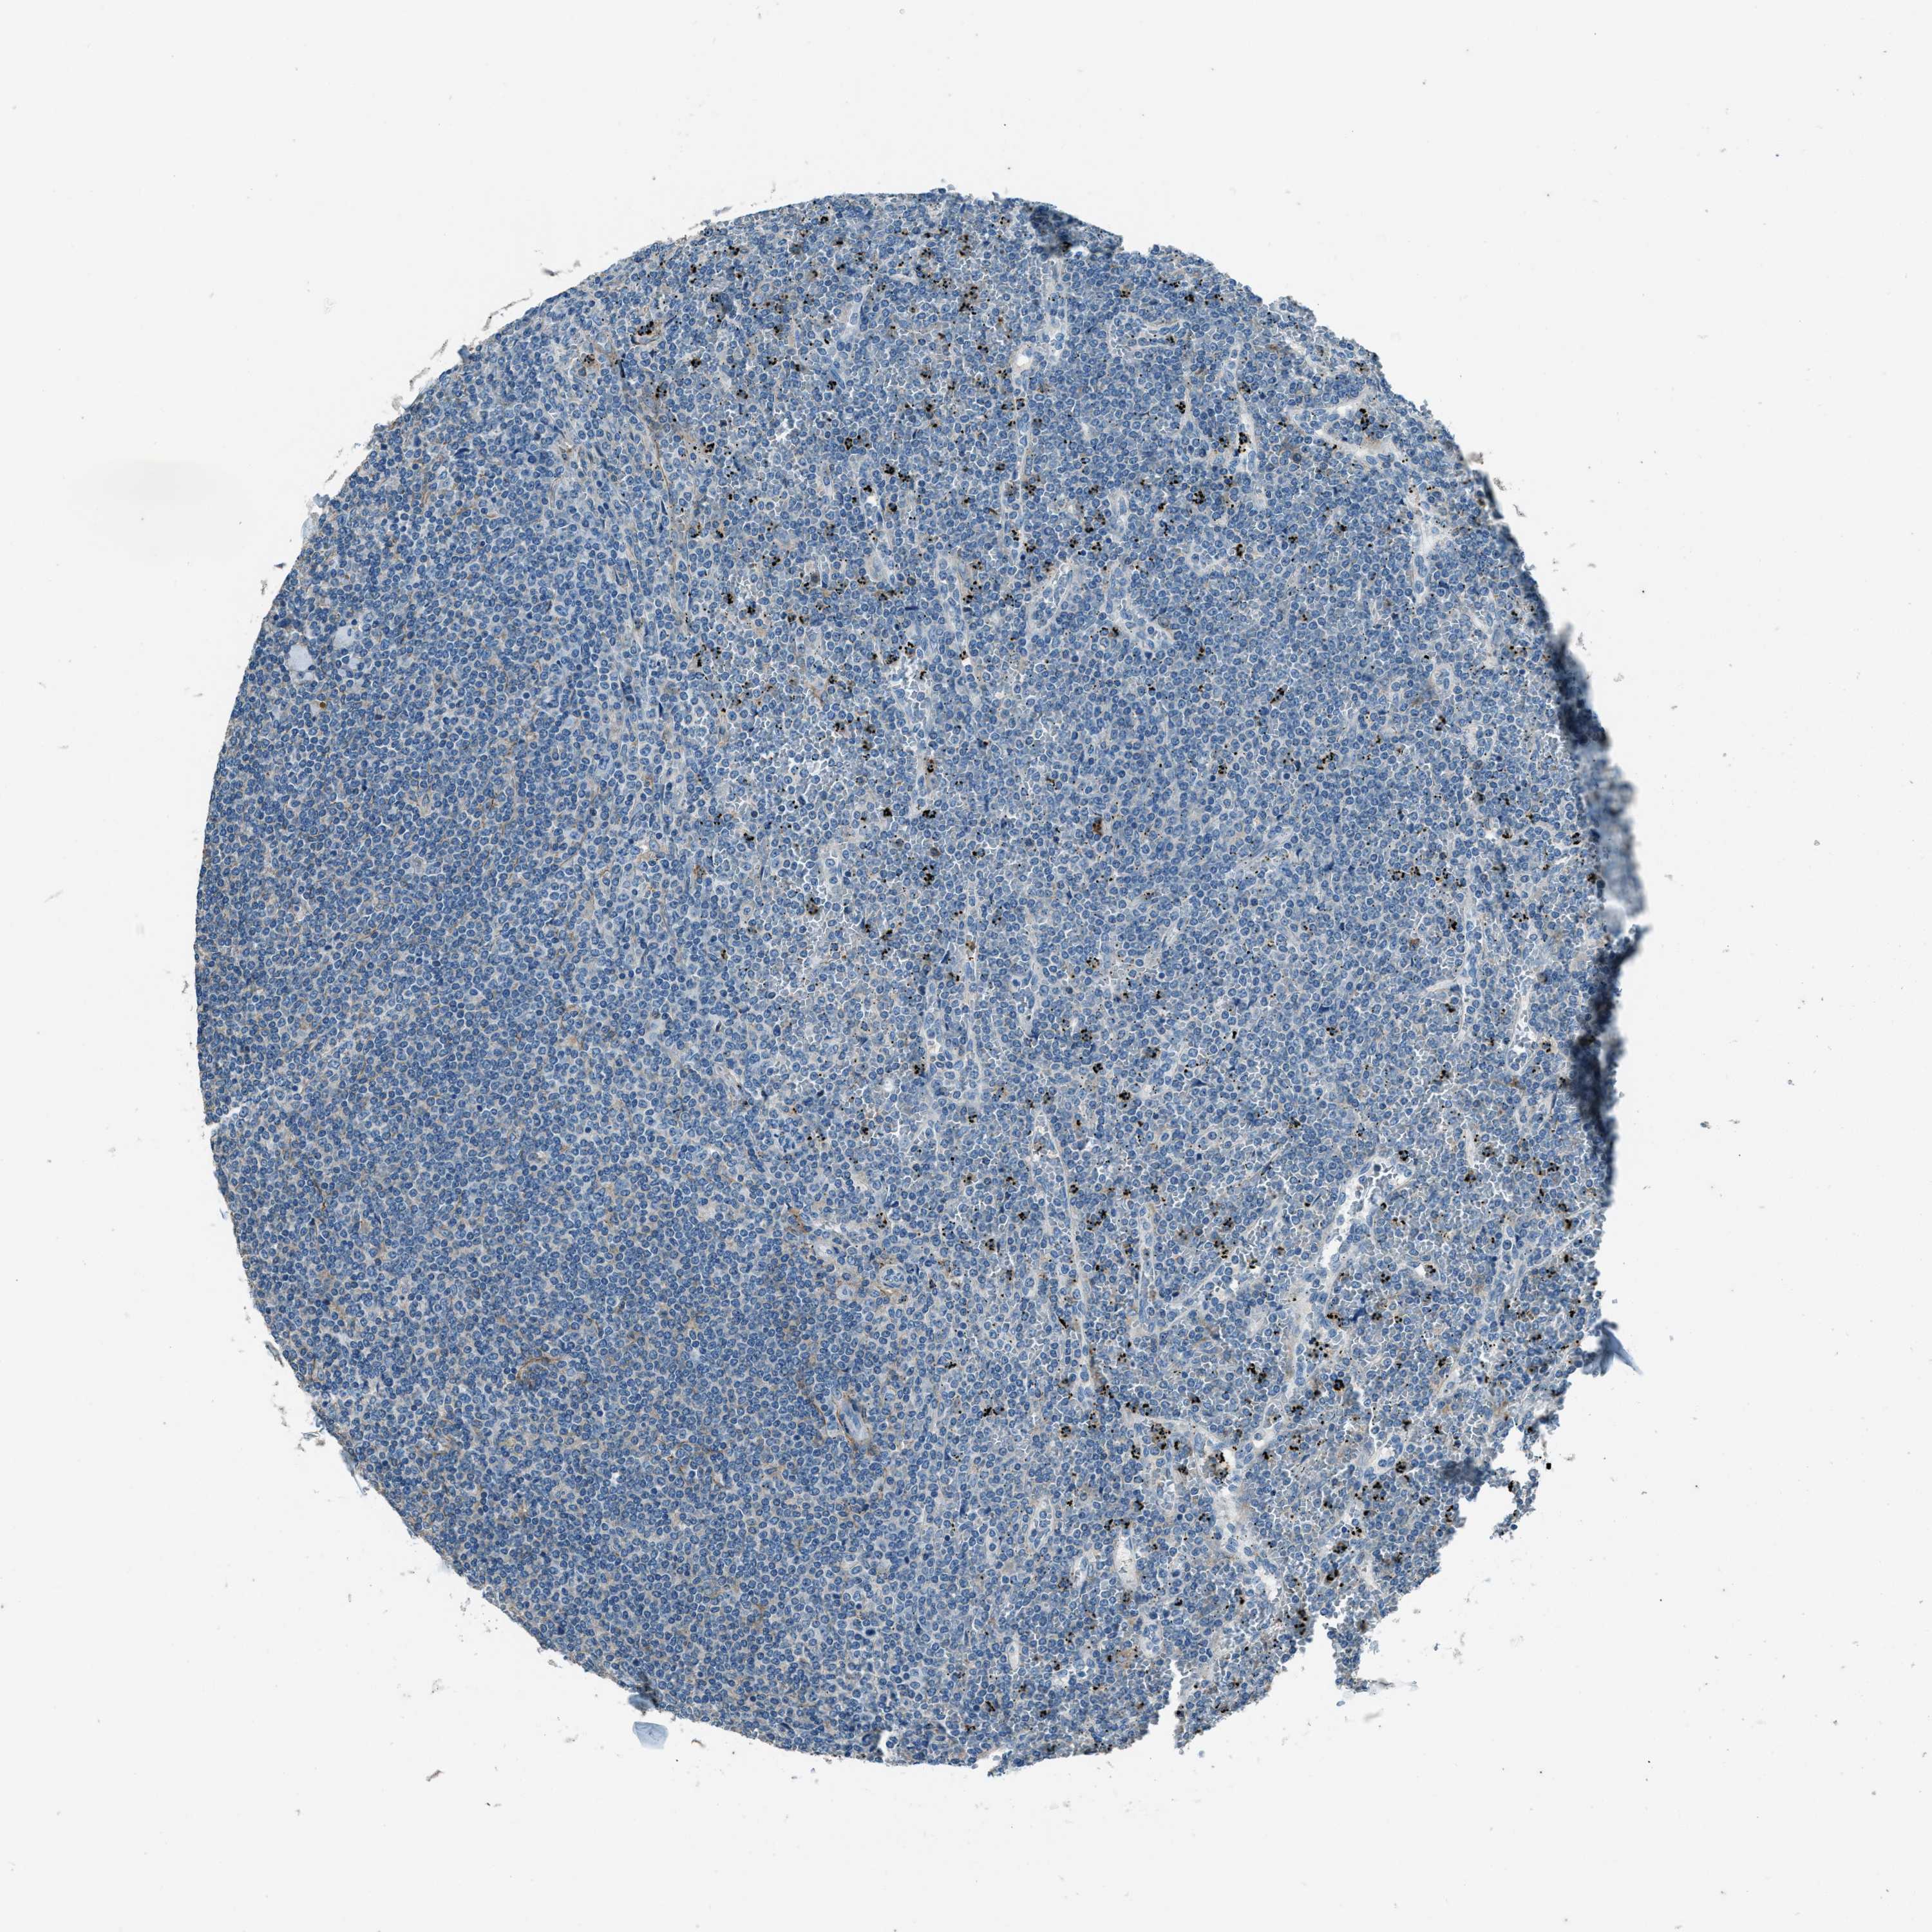

CANCER LYMPHOMA Show tissue menu

LYMPHOMA - Protein expressioni

A mouse-over function shows sample information and annotation data. Click on an image to view it in a full screen mode. Samples can be filtered based on level of antibody staining by selecting one or several of the following categories: high, medium, low and not detected. The assay and annotation is described here.

Each image is clickable and will lead to virtual microscopy that enables deeper exploration of all samples and also displays staining intensity scores, fraction scores and subcellular localization as well as patient and tissue information for each sample.

Antibody HPA020095

Antibody HPA020138

Antibody CAB010878

Antibody CAB080402

Hodgkin's disease, NOS

Malignant lymphoma, non-Hodgkin's type, High grade

Malignant lymphoma, non-Hodgkin's type, Low grade